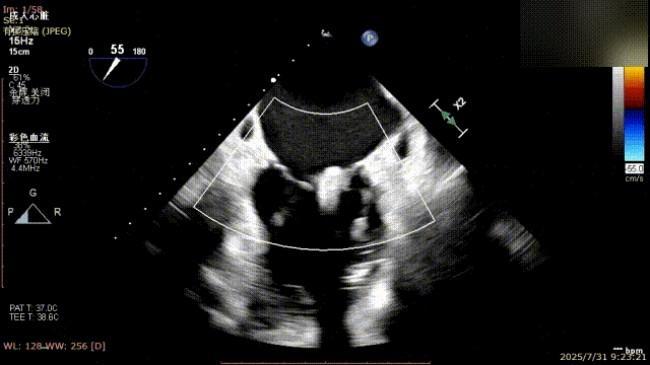

术前完善经食管超声评估,提示该患者双房大,二尖瓣重度反流4+伴后叶脱垂、后叶部分腱索断裂。根据评估结果,心脏大血管外科王安彪主任团队制定了周密的手术方案:植入一枚夹合器,钳夹P1区反流最大处,尽可能夹持全部后叶脱垂瓣叶组织,后续根据术中实时残余分流和跨瓣压差等指标,并依据实时超声监测调整治疗策略。

三维评估

二尖瓣P1脱垂偏心性返流术前影像